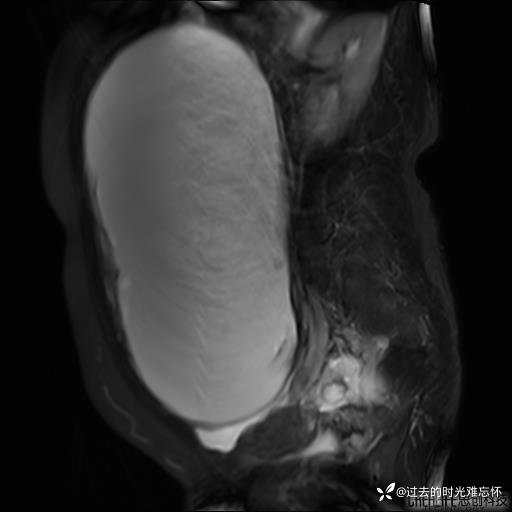

患者性别:女

患者年龄:65岁

主诉: 发现腹部隆起半年余。无其他明显不适。

浆液性囊腺瘤 (22)